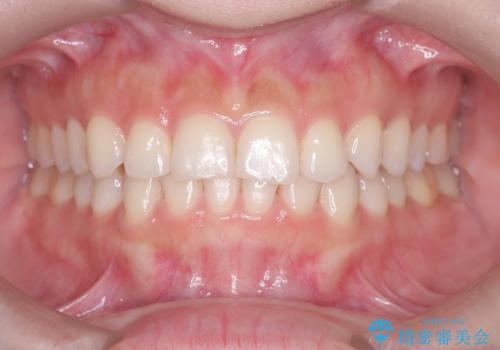

- 前歯のガタガタが気になるとのことでご相談いただきました。診察すると、歯列のスペースが不足し、前歯が重なっている状態でした。抜歯をせずに整えるため、歯と歯の間をわずかに削るIPR(歯列幅径削除)と、奥歯を後方へ動かす遠心移動を組み合わせてスペースを確保しながら並べる治療計画を立てました。

インビザラインを用いて歯を少しずつ移動させながら、IPRで微調整を行い、スペースを確保しました。また、奥歯を遠心移動させることで、前歯を自然な位置に並べることができました。治療後は、「ガタガタがなくなり、スムーズな歯並びになった」と患者様にもご満足いただきました。